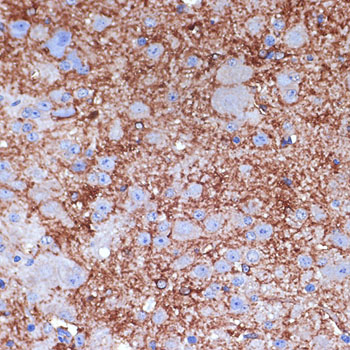

Immunohistochemistry of paraffin-embedded mouse spinal cord using NPY Rabbit pAb.